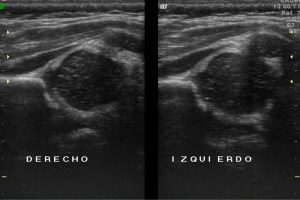

Diplomados en Ultrasonografía